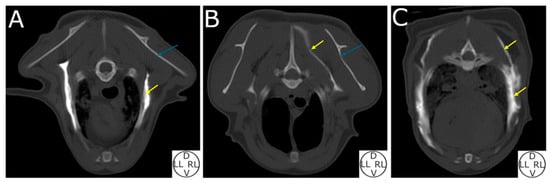

2.2.2. Computed Tomography (CT) Study

3.2.3. Computed Tomography (CT) Study